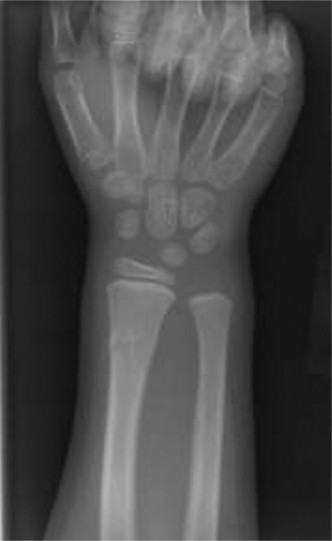

A 55-year-old female with a history of rheumatoid arthritis diagnosed at age 40 presents to your clinic compl…